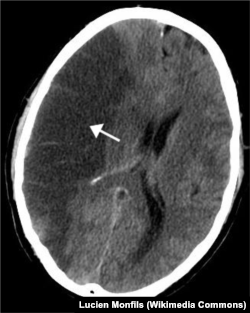

На сегодняшний день клиническая диагностика инсульта производится с помощью компьютерной томографии (КТ), которая определяет, произошло ли кровоизлияние в мозг. Стефен Меарис из университета Мангейма считает, что перспективным способом диагностики является магнитно-резонансная томография (МРТ) – более чувствительный по сравнению с КТ метод, требующий, однако, больше времени для проведения. МРТ позволяет получить более контрастное изображение с более четкой различимостью белого и серого вещества, лучшим качеством изображения базальных, стволовых, корковых структур по сравнению с КТ. Впрочем, МРТ и КТ могут применяться как взаимодополняющие методы диагностики.